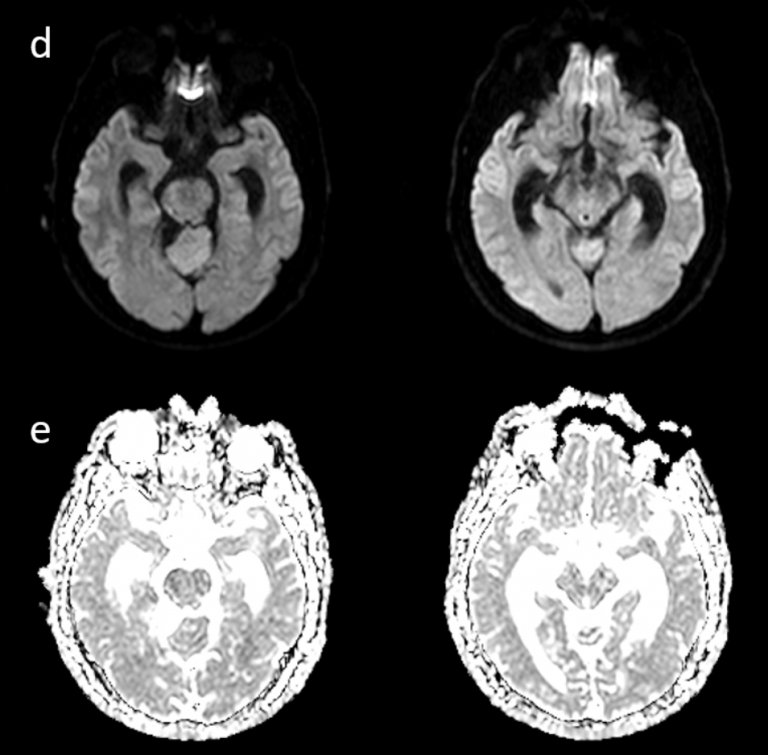

Resonancia magnética: secuencias ponderadas en T1 con gadolinio en plano axial (A), sagital (B) y coronal (C): Masa extraaxial de aspecto heterogéneo, bien definida, con un intenso realce periférico, de 42 x 41 x 38 mm (AP x TR x CC) en la línea media frontobasal. La lesión está en contacto con la lámina cribiforme y parece originarse del bulbo y tracto olfatorio izquierdo. Aisladas formaciones quísticas periféricas. Secuencia ponderada en T2 plano coronal (D): extensa área de hiperseñal T2 que se extiende por la sustancia blanca del lóbulo frontal izquierdo.

La RM es la técnica de elección para su diagnóstico, mostrando una masa extraaxial bien delimitada, de intensidad baja o intermedia en imágenes ponderadas en T1 e hiperintensas en T2. La hiperintensidad en T2 puede ser homogénea o mostrar un aspecto “en diana” con alta intensidad en la periferia de la lesión.